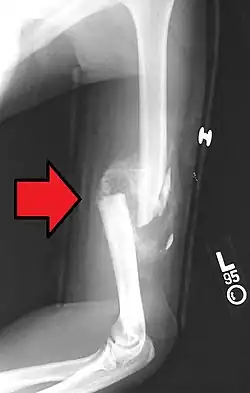

Distal

Distal humerus fractures usually occur as a result of physical trauma to the elbow region. If the elbow is bent during the trauma, then the olecranon is driven upward, producing a T- or Y-shaped fracture or displacing one of the condyles.[7]

Definitive diagnosis of humerus fractures is typically made through radiographic imaging. For proximal fractures, X-rays can be taken from a scapular anteroposterior (AP) view, which takes an image of the front of the shoulder region from an angle, a scapular Y view, which takes an image of the back of the shoulder region from an angle, and an axillar lateral view, which has the patient lie on his or her back, lift the bottom half of the arm up to the side, and have an image taken of the axilla region underneath the shoulder.[9] Fractures of the humerus shaft are usually correctly identified with radiographic images taken from the AP and lateral viewpoints.[12] Damage to the radial nerve from a shaft fracture can be identified by an inability to bend the hand backwards or by decreased sensation in the back of the hand.[5] Images of the distal region are often of poor quality due to the patient being unable to extend the elbow because of pain. If a severe distal fracture is suspected, then a computed tomography (CT) scan can provide greater detail of the fracture. Nondisplaced distal fractures may not be directly visible; they may only be visible due to fat being displaced because of internal bleeding in the elbow.[7]

Fractures of the humerus are classified based on the location of the fracture and then by the type of fracture. There are three locations that humerus fractures occur: at the proximal location, which is the top of the humerus near the shoulder, in the middle, which is at the shaft of the humerus, and the distal location, which is the bottom of the humerus near the elbow.[9] Proximal fractures are classified into one of four types of fractures based on the displacement of the greater tubercle, the lesser tubercle, the surgical neck, and the anatomical neck, which are the four parts of the proximal humerus, with fracture displacement being defined as at least one centimeter of separation or an angulation greater than 45 degrees. One-part fractures involve no displacement of any parts of the humerus, two-part fractures have one part displaced relative to the other three; three-part fractures have two displaced fragments, and four-part fractures have all fragments displaced from each other.[13][14][3] Fractures of the humerus shaft are subdivided into transverse fractures, spiral fractures, "butterfly" fractures, which are a combination of transverse and spiral fractures, and pathological fractures, which are fractures caused by medical conditions.[12] Distal fractures are split between supracondylar fractures, which are transverse fractures above the two condyles at the bottom of the humerus, and intercondylar fractures, which involve a T- or Y-shaped fracture that splits the condyles.[7]